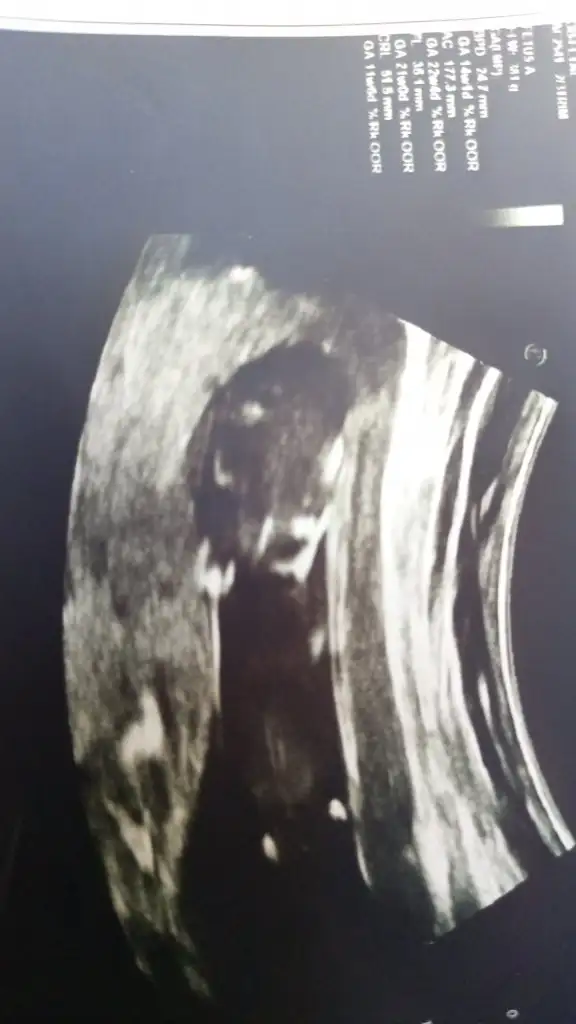

Ikra meyra Ikra meyra merhabalar ☺️ Bize de bir tahminde bulunabilir misin? 💐

Benim miniğe de bakabilir misiniz acaba😊 sat a göre 10+5 usg e göre 11+3🍀